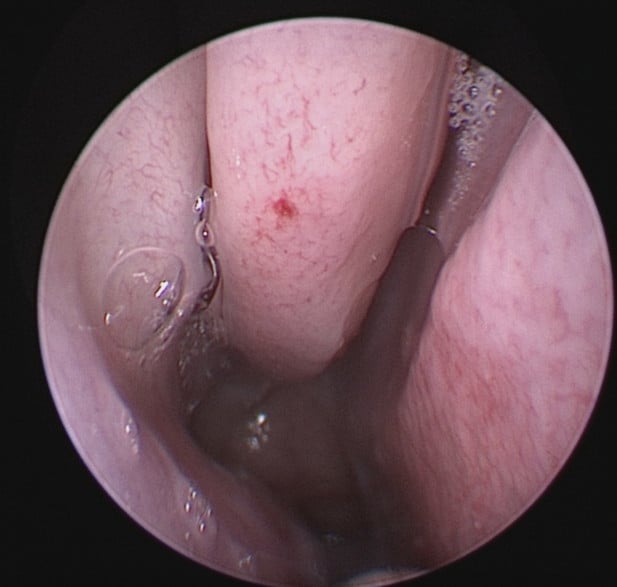

• Nasal endoscopy to identify bleeding points